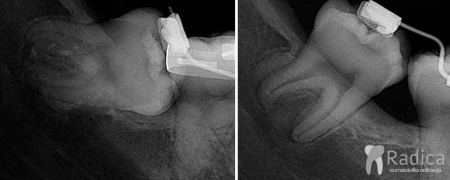

U sljedećem primjeru je pacijent došao sa impaktiranom mliječnom i stalnom donjom „peticom“. U terapiji je prvo korišten lingvalni luk za čuvanje prostora, a dalje je nastavljeno s fiksnim aparatom.